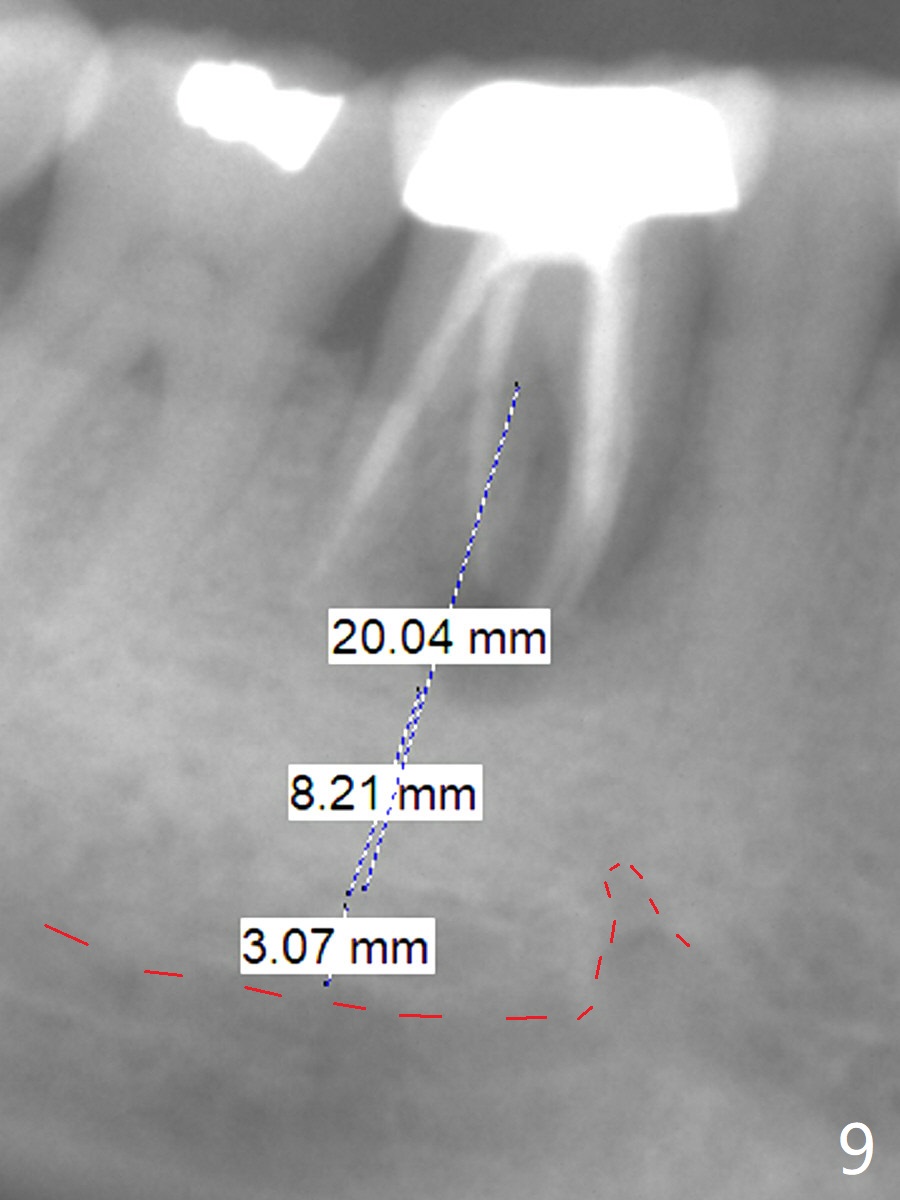

A 55-year-old woman has severe bone loss (Fig.1 with buccal and lingual fistulae) around the mesial (M in Fig.2) and distolingual (DL) roots. If there is a septum after extraction (Fig.3 S), osteotomy will be established in the septum to enhance primary stability (Fig.4). When the septum cannot be saved (Fig.5), osteotomy is to be initiated in the septal slope oblique (Fig.6 <). The osteotomy will be straightened once an entry is made (Fig.7). The initial osteotomy is slightly distal, since as osteotomy increases (Fig.8 blue), it tends to shift mesial (arrow). In addition, the apex of the 2nd bicuspid tilts distal (yellow dashed line). Depth of osteotomy is 20 mm (crest, Fig.9) or 18 mm (septum) so that 8 mm of the native bone can be obtained with 3 mm clearance from the Inferior Alveolar Canal (red dashed line). PRFx2 is required (seems not done).